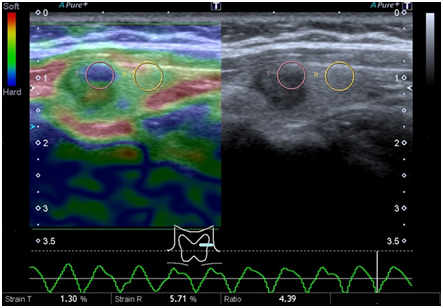

We report a case of PTC discovered by E. A 54years old female with a studied thyroid nodule during 5years, was performed US and E. The nodule was described as circumscribed, markedly hypoechoic, with no vessels, in thyroid left lobe. With a diameter of 9mm, stable during the time. E shown an inner area of stiffness (3mm size) and an outer area softer. Thyroid homogeneous echogenicity, without evidence of another nodule. We performed FNA E-guided of stiffness area. The cytology reported compact clusters of follicular cells with moderate anisokaryosis, empty nuclei and papillary branches, with microcalcification, that indicated suspicion of papillary carcinoma (Bethesda V). At surgery cancer had spread to local lymph nodes. The patient was undergone completion thyroidectomy and received radioactive iodine treatment (Figure 1) (Figure 2).

Figure 1 Gray scale (left) and Power Doppler (right) of thyroid nodule in the left lobule that shows no vascularization.